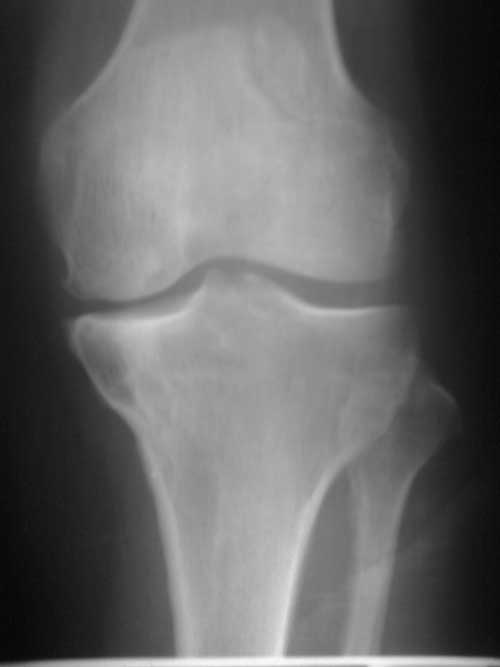

标题: X7063:女、40岁、左膝间歇性疼痛一年余,否认有外伤史。 [打印本页]

标题: X7063:女、40岁、左膝间歇性疼痛一年余,否认有外伤史。

1  左膝退变并关节面下骨质囊变。2 二分髌骨。

1)左膝关节退行性骨关节病,左胫骨上端邻关节骨囊肿。2 )二分髌骨。

邻关节骨囊肿或软骨下假囊肿,二分髌骨。

左膝关节退行性骨关节病,左胫骨上端骨囊肿。二分髌骨。

)左膝关节退行性骨关节病,左胫骨上端邻关节骨囊肿。2 )二分髌骨。